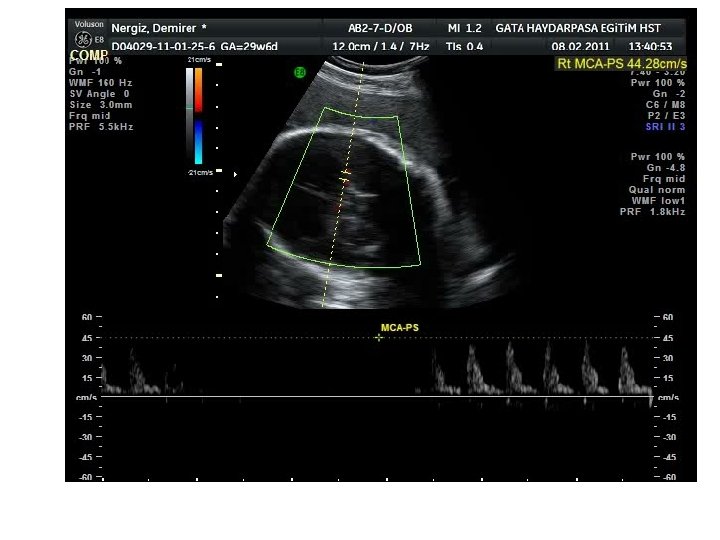

Tanı Yöntemleri-Ultrasound-MCA Doppler – Şiddetli anemik fetusta periferal dokulara oksijen iletimini artırmak için kardiak output artar. – Kan viskozitesi azalır. Doppler ultrasonla fetal MCA pik sistolic hız (PSH) değerlendirmesi fetal aneminin öngörüsünde kullanılmaktadır. Gebelik haftasına göre 1. 5 MOM’dan (multiples of the median) daha yüksek PSH değerleri, % 88 sensitivite ve % 89 negatif prediktif değerle orta derecede-ağır fetal anemiyi öngörür. Mari G. Noninvasive diagnosis by Doppler ultrasonography of fetal anemia due to maternal red-cell alloimmunization. N Engl J Med. 2000; 342: 9 -14

• Maternal batın duvarına yakın MCA tercih edilir (Posterior damar da eşit sonuç verir). • İnsonasyon açısı mümkün olduğunca sıfıra yakın olmalı. • Pratikte açı düzeltmesine gerek yok. • Doppler örnekleme aralığı (sample gate) MCA’in karotid sifondan (Willis halkasından) çıktığı proksimal kısmına yerleştirilir. • Daha distalden yapılan ölçümlerde pik sistolik akım hızı daha düşük olacağından yanlış sonuç elde edilir.

• MCA ölçümleri 18. gebelik haftasından itibaren güvenilir olarak yapılabilir. • Ölçümler, trende göre 1 -2 hafta ara ile tekrarlanmalı. • Dikkat!!! – MCA’in distalinden yapılan ölçümlerde yanıltıcı olarak daha düşük MCA pik akım hızı elde edilir. – Fetal hareket sırasında fetal kalp hızı arttığından pik akım hızı daha düşük çıkar (özellikle geç üçüncü trimesterde) – Antenatal steroid uygulamasını takiben MCA pik akım hızında geçici azalma olur (bu etki son dozdan itibaren 24 -48 saat devam eder).